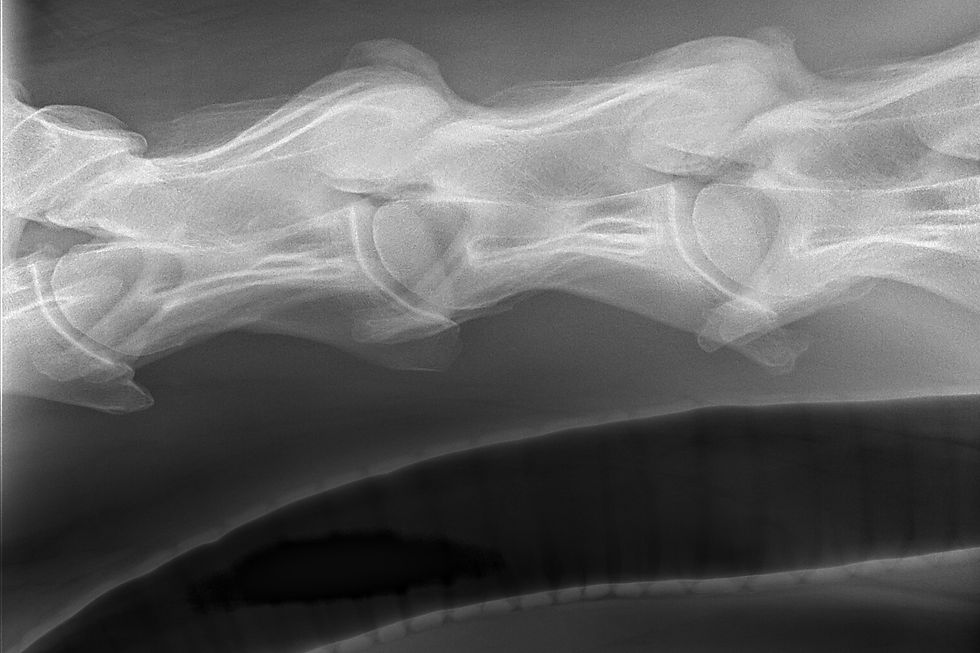

Radiographs are typically the first imaging step, focusing on C6, C7, and T1. Veterinarians evaluate bone shape, symmetry, and attachment points, looking for missing structures, fused elements, or rib transpositions. Imaging this region can be technically difficult due to the horse’s size and heavy musculature, and multiple views are often required. Larger horses may need referral to facilities with high-powered imaging systems.